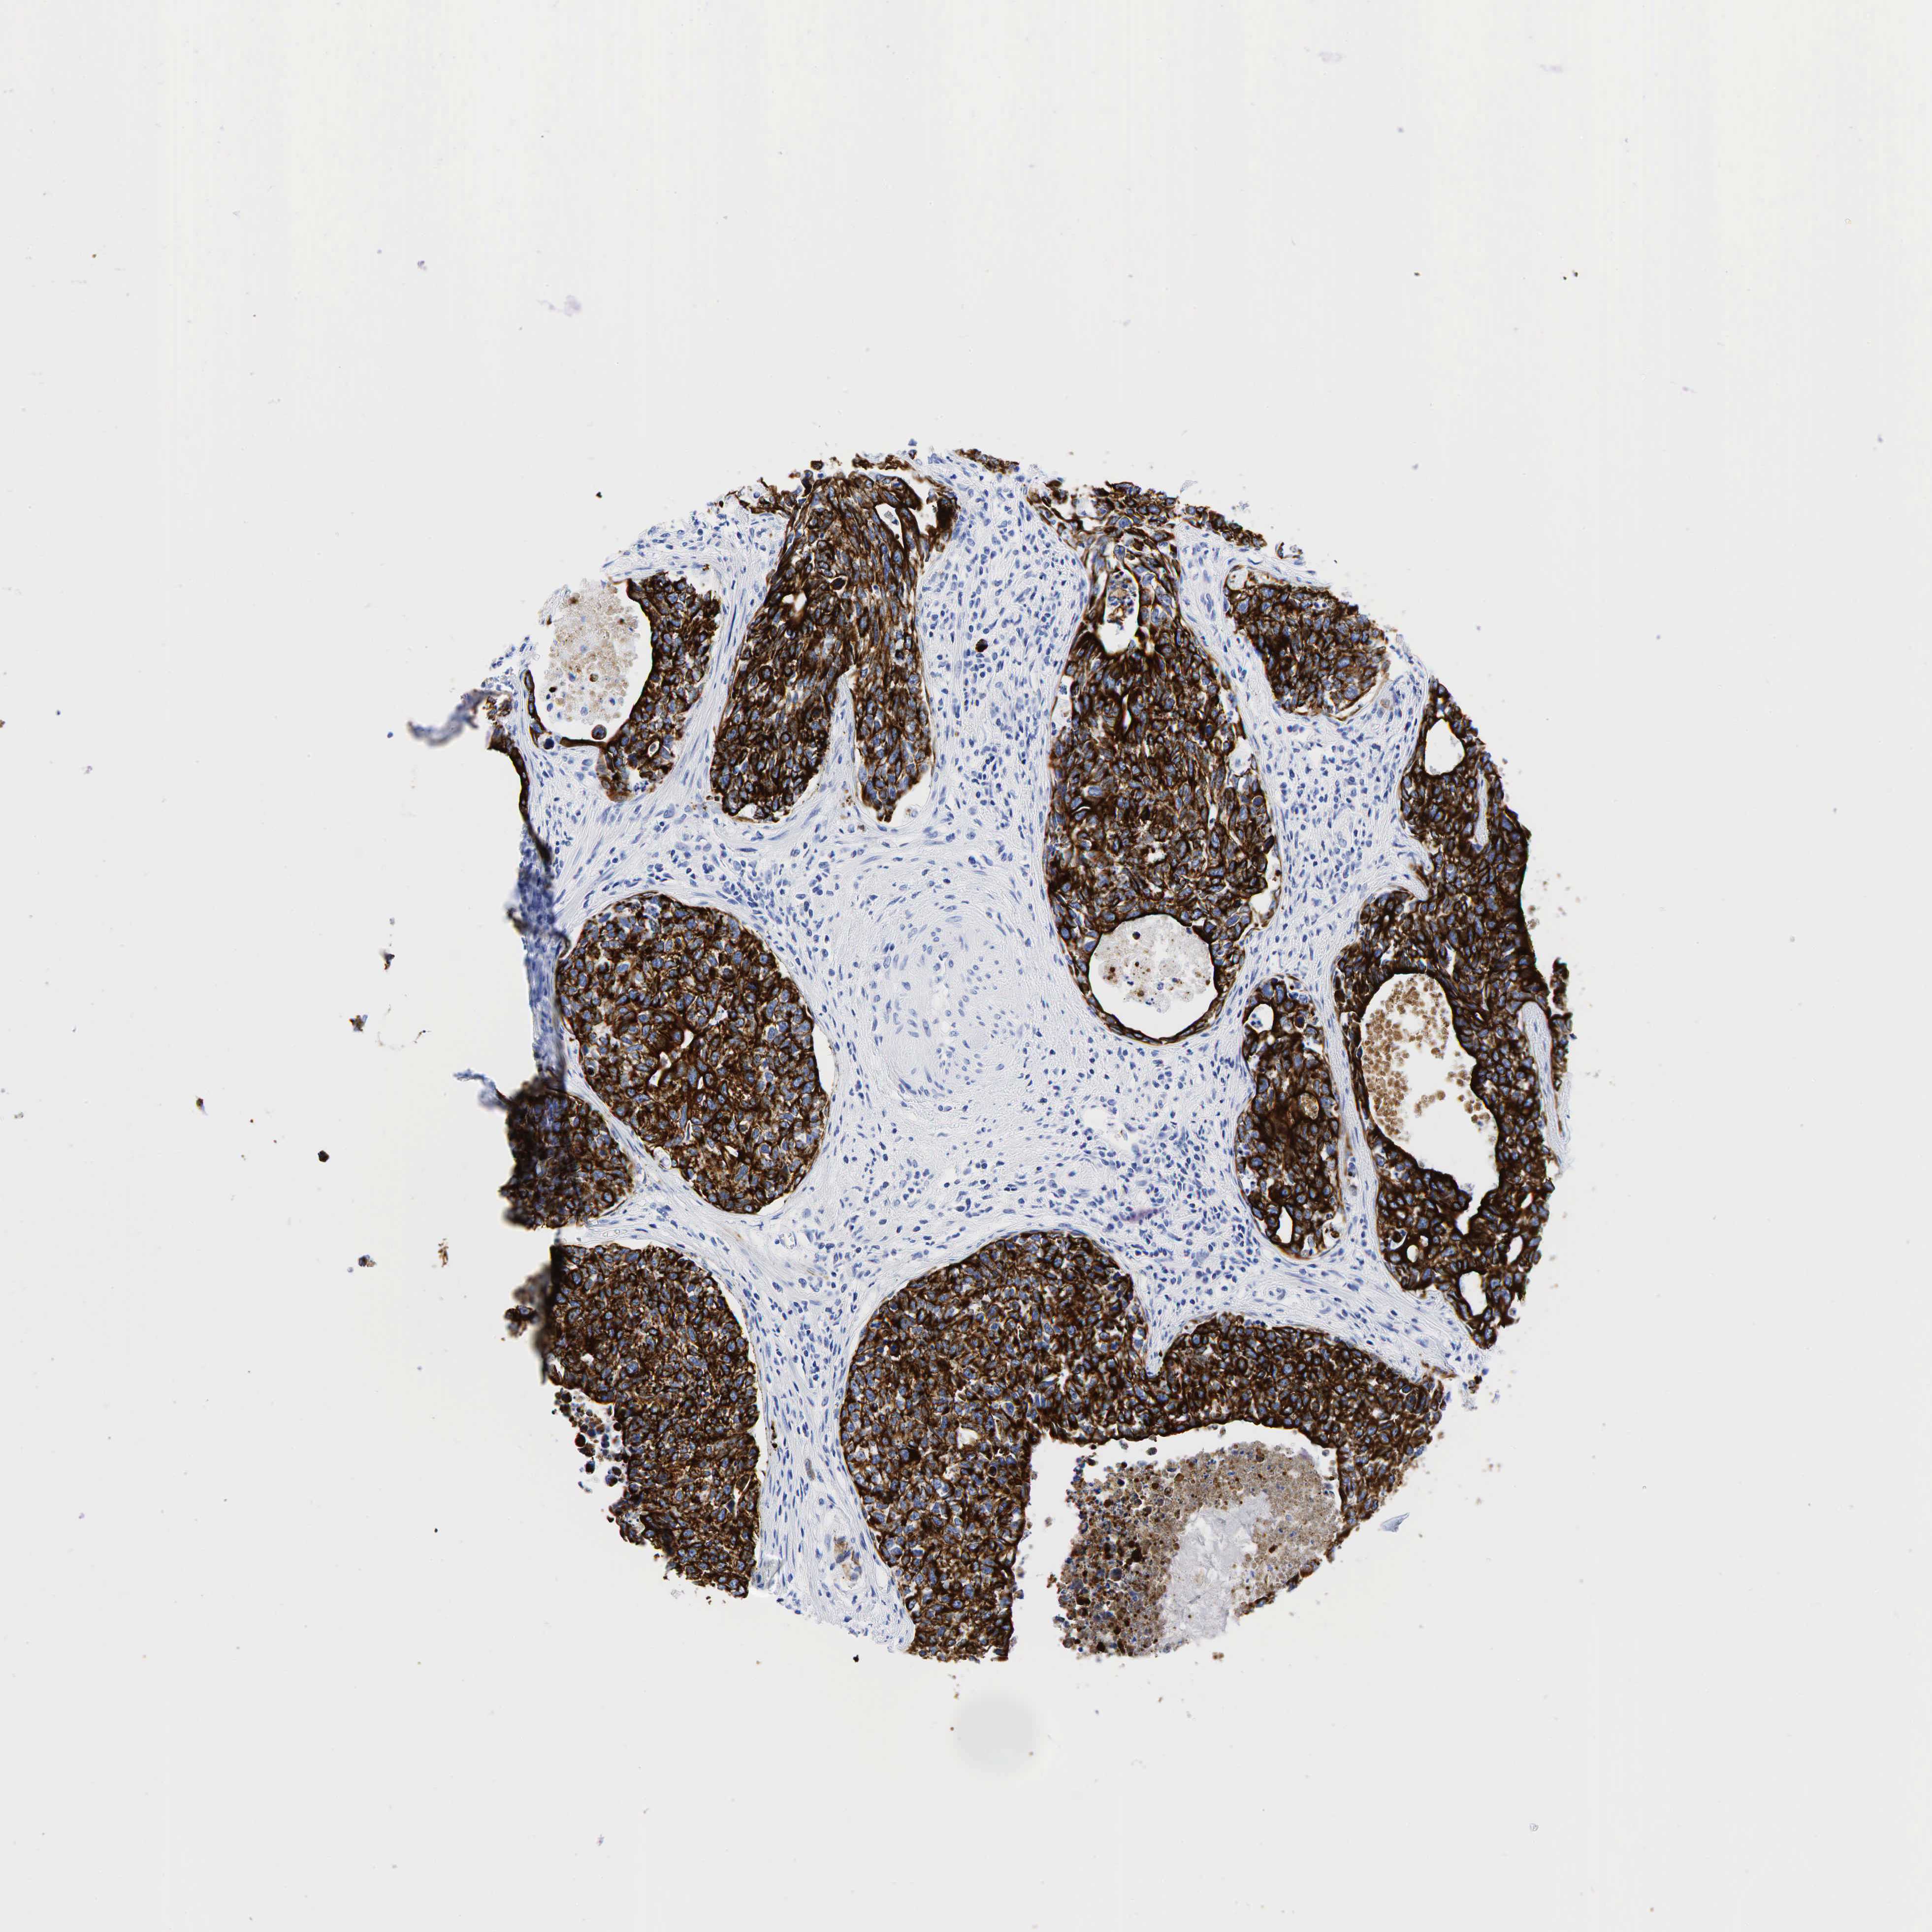

UROTHELIAL CANCER - Protein expressioni

A mouse-over function shows sample information and annotation data. Click on an image to view it in a full screen mode. Samples can be filtered based on level of antibody staining by selecting one or several of the following categories: high, medium, low and not detected. The assay and annotation is described here.

Antibody stainingi

Antibody staining in the annotated cell types in the current human tissue is reported as not detected, low, medium, or high, based on conventional immunohistochemistry profiling in selected tissues. This score is based on the combination of the staining intensity and fraction of stained cells.

Each image is clickable and will lead to virtual microscopy that enables deeper exploration of all samples and also displays staining intensity scores, fraction scores and subcellular localization as well as patient and tissue information for each sample.

Antibody HPA002465

Antibody CAB000031

Staining

High

Medium

Low

Not detected

Intensity

Strong

Moderate

Weak

Negative

Quantity

>75%

75%-25%

<25%

None

Location

Nuclear

Cytoplasmic/membranous

Cytoplasmic/membranous,nuclear

Urothelial carcinoma, High grade